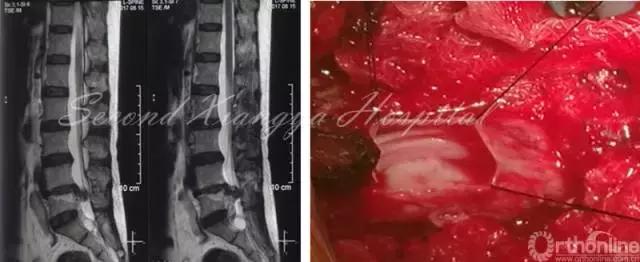

F,46岁,L4/5 LDH,外院行PETD后出现马尾综合征,转入中南大学湘雅二医院急诊行开放减压,术中发现髓核脱入到硬膜内。